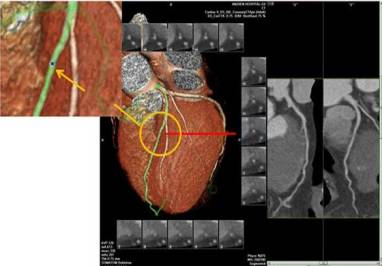

在临床上我们通常看到的冠脉CTA图像有三个部分,即表面成像(VR)、曲面重建(CPR)和冠脉探针 ,每一部分都有不同的意义。

■ 表面成像(VR)

我们拿到一份冠脉CT影像首先要看VR像,从VR像我们主要是观察冠状动脉的走形、起源以及桥血管的走形。需要注意的是,VR图像不能判断冠状动脉是否狭窄,同一个人随着成像条件的变化,管腔的狭窄显示程度会发生改变。

■ 冠脉探针

通过冠脉探针可以显示管腔横截面,以便更好的观察斑块形态。通常在VR项可以显示探针的位置,以此点为中心,向上、向下各显示7个断层,每个断层1 mm,加上所选取的一层,共显示15 mm长的冠状动脉管腔横截面,冠脉探针与CPR相结合,能更精确的判断冠脉管腔狭窄程度。而探针显示的某个特点也可以初步判断斑块的稳定性,如点状钙化、指环征等。